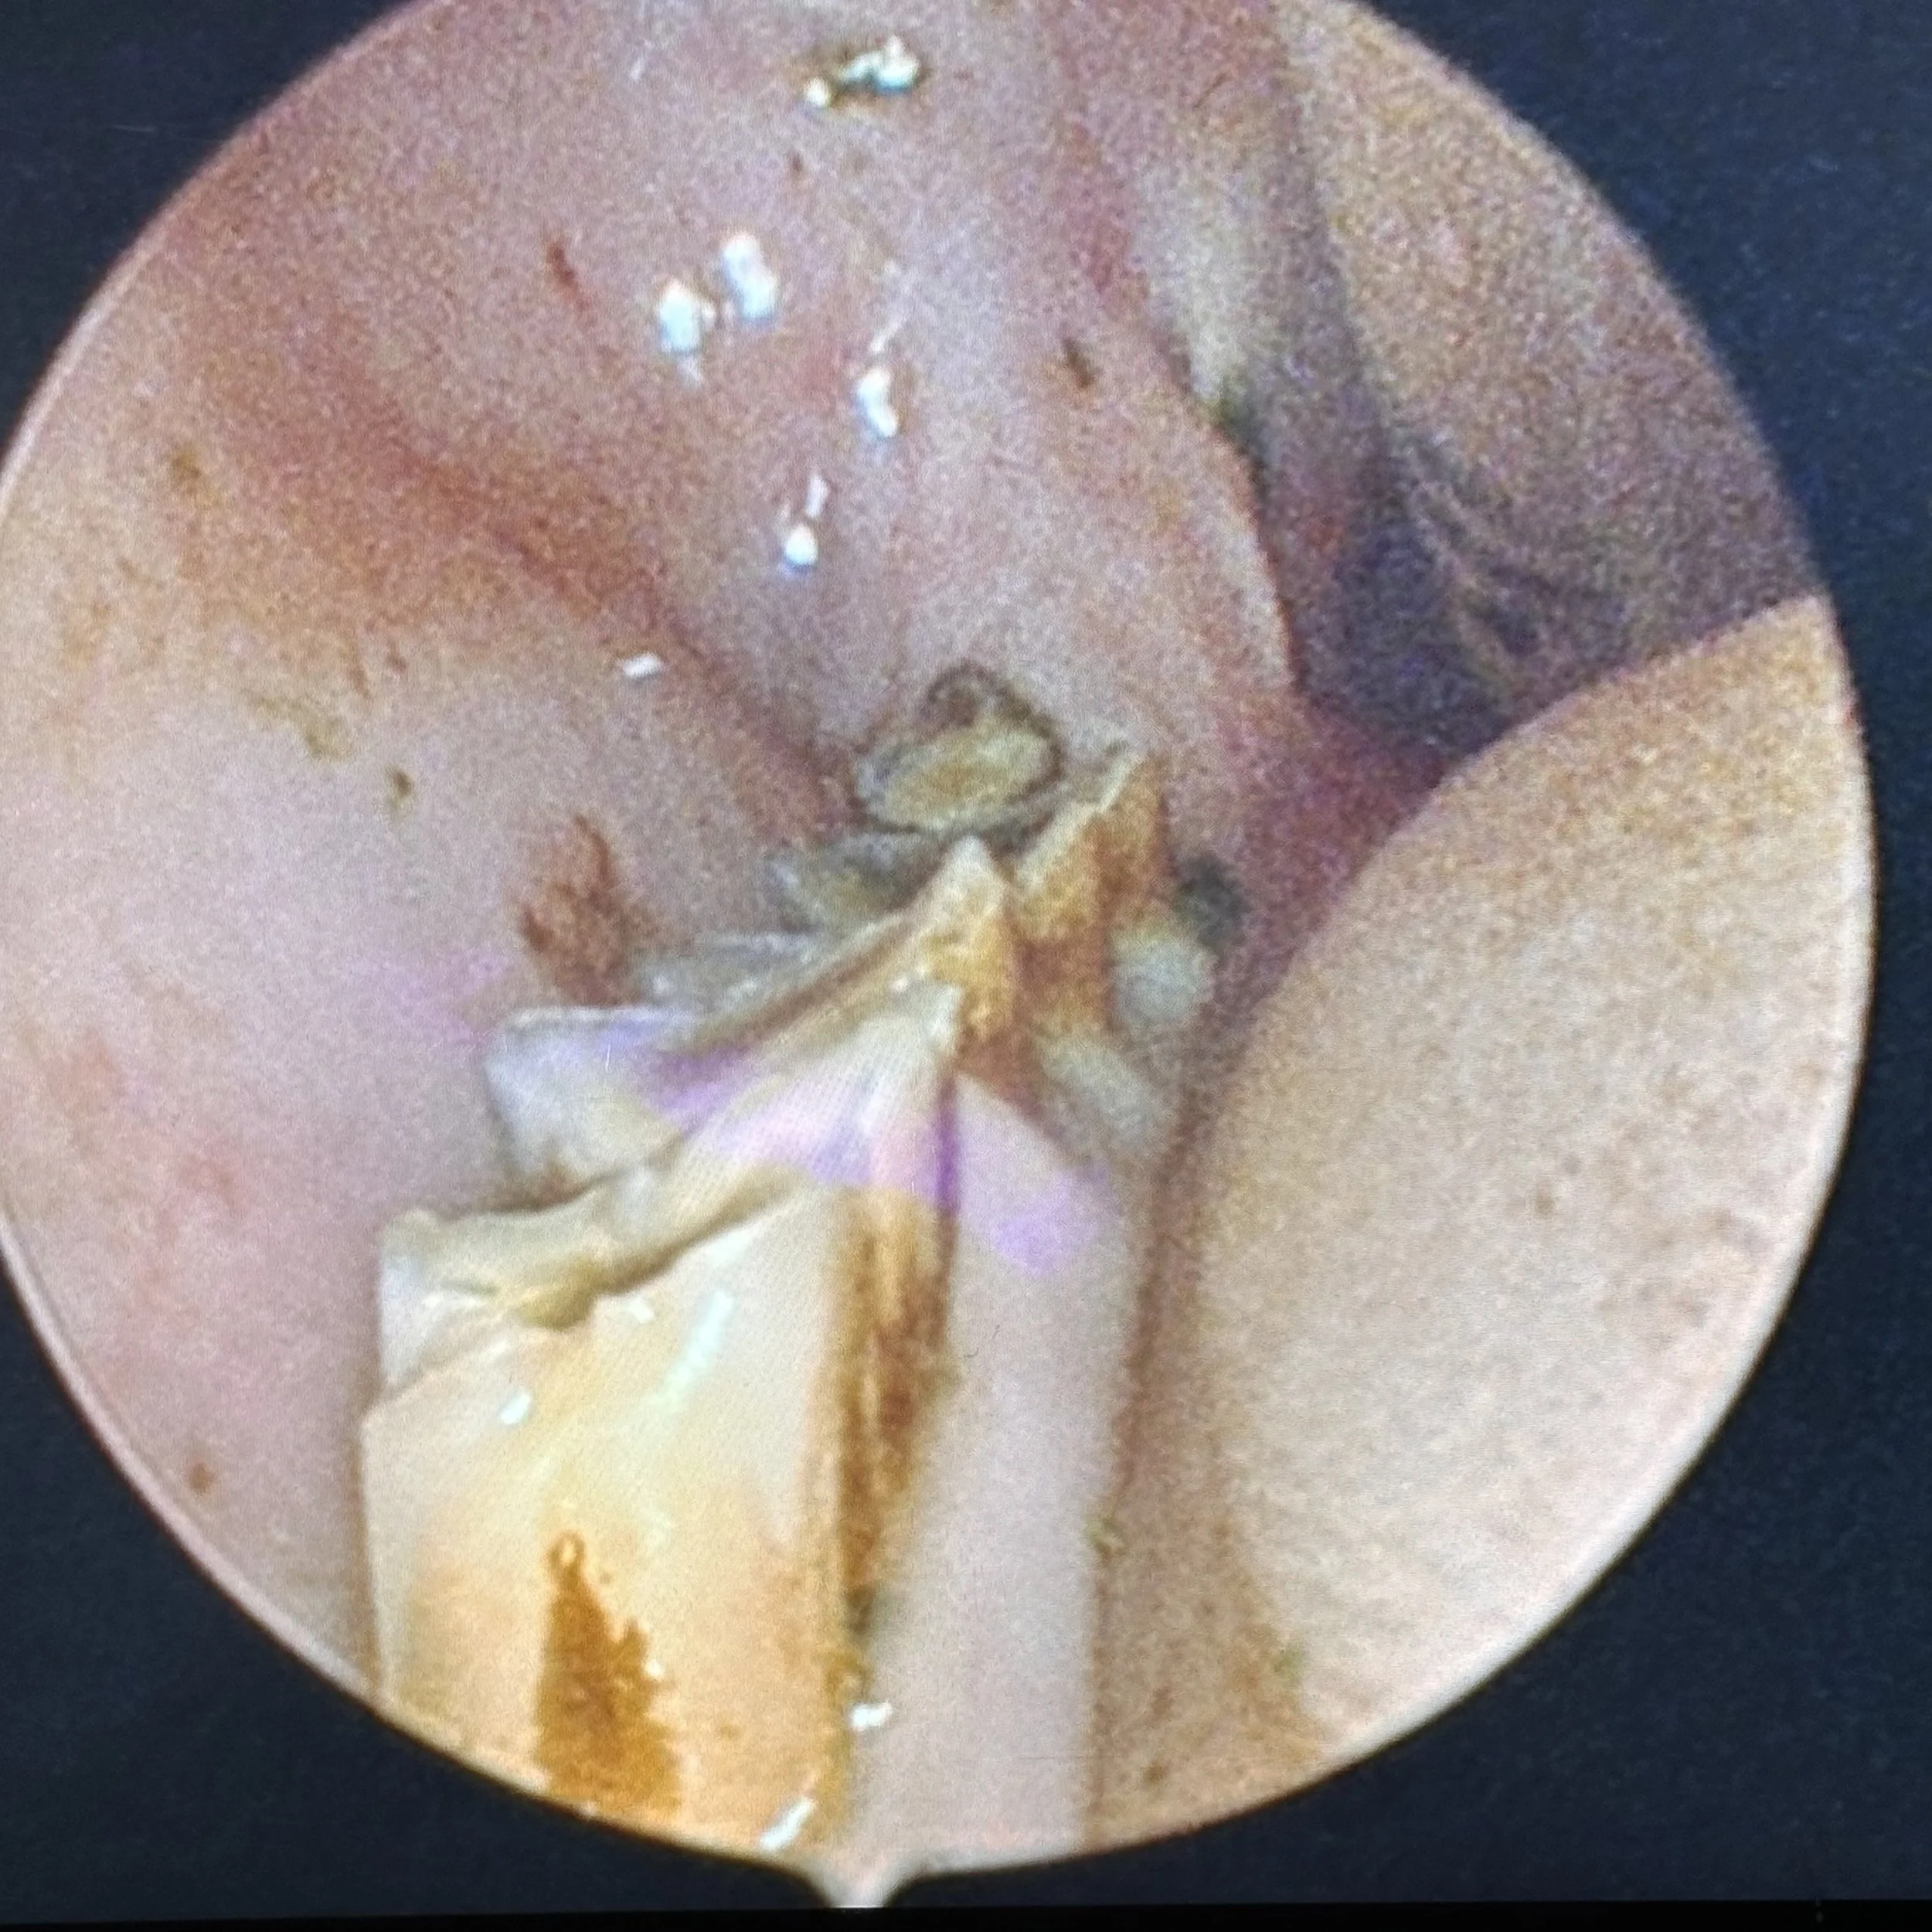

These photos show spurs on the rear molars. Having your rabbit’s teeth - including the back teeth, checked yearly is essential.